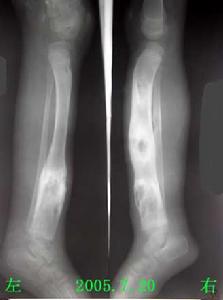

初生並無不良,股骨頭二次骨化中心出現延遲往往是最早的x線徵象,可以延遲到1—2歲才出現。股骨頭骺不規則,密度增加、不均勻、斑駁、破碎,很像Perthes病的表現。其他部位如股骨遠端,脛骨近端,脛骨遠端,肘、腕關節骨骺,均可有程度不等的變異,腕骨和跗骨間可發生融合。待發育成熟骨骺閉合後,關節面不規則,呈桑椹狀,股骨頸乾角減小,短頸、扁平髖,膝關節力線不良,內翻或外翻,踝關節踝穴變形,距骨滑車塌陷變扁,距骨頸變短,距骨頭扁平,距骨缺血壞死,跗骨扭曲,趾骨短縮,肘關節、腕關節間隙明顯變窄,尺撓骨發育不對稱,腕骨扭曲,掌骨變短。個別病例累及椎體,表現為椎體不規則,前方稍呈楔狀變形。

患者,男,10歲,全身關節痛5年余,近1年來,全身關節疼痛更顯著,活動後易疲勞。其家族無其他人患此病。查體:身高106cm,體重26kg,智力尚正常,步態不穩。“X”型腿,雙手粗而短,指間關節腫脹,雙肘、雙膝、雙踝粗大,無紅熱,脊柱後凸,四肢與軀幹基本均稱。實驗室檢查:無不良發現。X線表現:兩側骨骺對稱性受累,骨骺發育小及變扁,可見呈分節或斑點狀,邊緣不規則,但無硬化帶。雙手掌指骨短,乾骺端粗大,雙舟骨不規則狀變形,各腕骨間骨間隙變窄。脊柱各椎體稍變扁,上下緣不規則且毛糙,頸椎下各

椎間隙稍變窄,腰椎第3、4、5椎體前後徑小,且胸腰段以胸11椎體至腰1椎體為中心後凸畸形。骨盆變窄,呈狹長型改變,雙股骨頭骨骺變扁平,並見有分節及斑點狀改變,股骨頸變短,髖臼變淺,雙膝關節間隙外寬內窄,雙側脛骨遠端骨骺外側部分發育不良,較細小,骨骺呈尖端指向外側之楔形,雙踝關節面傾斜。

多發性骨骺發育不良多發性骨骺發育不良據資料於1921年首先被Barringten-Ward報導,1947年命名。本病僅侵犯骨骺軟骨,主要為軟骨發育過程中先期鈣化帶區的軟骨細胞未成熟,數量減少、排列不規整,致骨化障礙。本病男女均可發病,約50%系家族性發病。一般於4歲以後出現症狀,表現為關節疼痛,運動障礙和步態不穩。病變只侵犯及骨骺,以兒童時期最顯著,尤其以11-12歲症狀最明顯,青春期後隨年齡增長症狀可改善。身材較短小,四肢與軀幹基本勻稱,手足可粗短。表現為骨骺發育小而且變扁,邊緣不規則,可呈分節或斑點狀,但無硬化。管狀骨變短,關節面傾斜,脊柱後凸畸形,脛骨遠端骨骺有特徵性表現。隨年齡增長而乾骺端變小、扁平及關節畸形,較早地引起退行性骨關節病。本病須與軟骨發育不全、乾骺發育不良等骨關節發育障礙相鑑別。如能結合病史及其特徵性X線表現,是不難鑑別的。